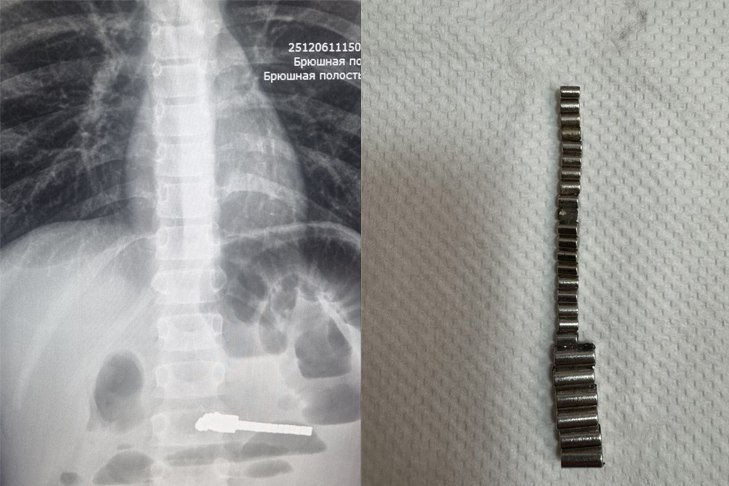

25 магнитиков извлекли из кишечника ребенка хирурги Детской городской клинической больницы № 1 Новосибирска.

«Особую тревогу вызывают случаи, связанные с магнитами. Недавно в наше приемное отделение поступил ребенок с жалобами на многократную рвоту и сильные боли в животе. Обследование выявило множественные рентгенконтрастные предметы в кишечнике и явные признаки кишечной непроходимости. В ходе экстренной операции было удалено 25 магнитов», – рассказала главный врач ДГКБ № 1 Евгения Аверкина.

Магниты могут притягиваться друг к другу через стенки кишечника, это приводит к кишечной непроходимости, некрозу, перфорации кишечника и формированию свищей. Длительное нахождение 25 магнитов в ЖКТ у этого пациента привело к серьезным осложнениям. Как добавили в новосибирском минздраве, сейчас жизни ребенка ничего не угрожает, операция прошла успешно.